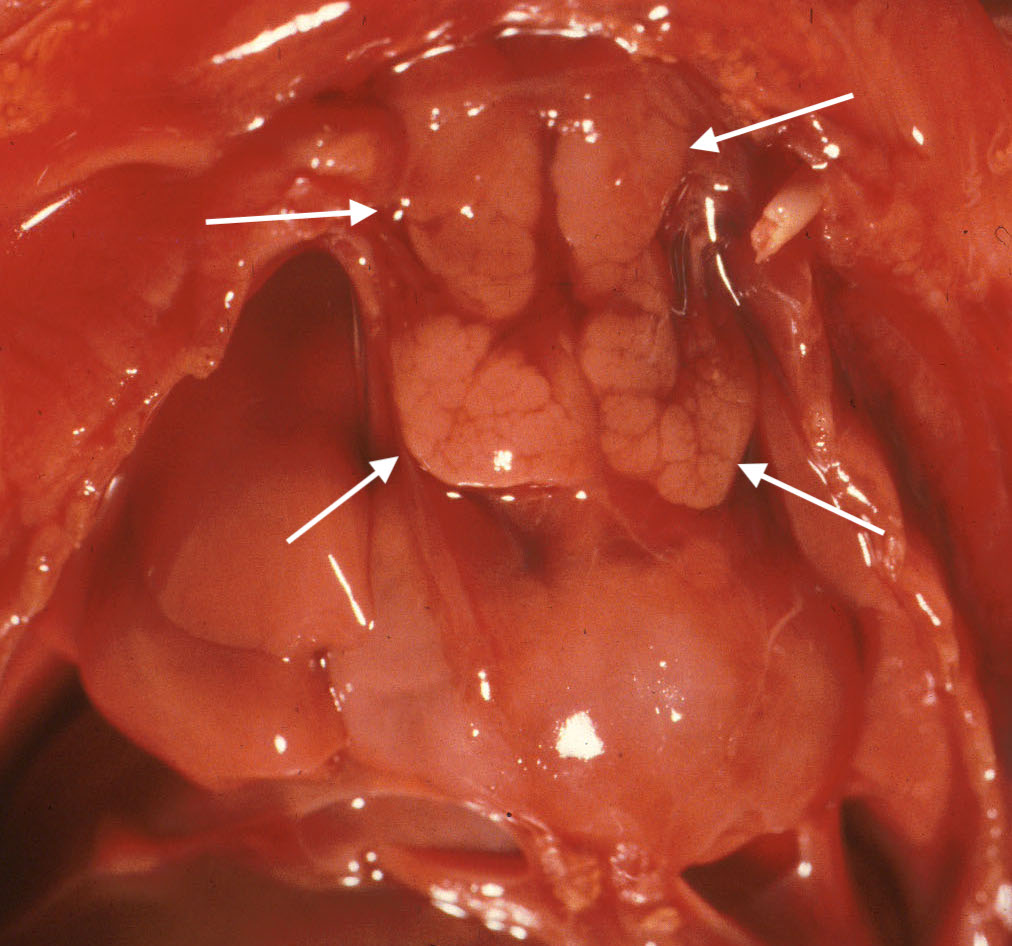

The normal thymus is bilaterally symmetrical with a narrow cervical portion and a larger, pyramidal thoracic portion. It lies anterior to the innominate vein and pericardium. Abnormal locations can be asymmetrical between lobes. The thymus may be more cervical, posterior to the great veins or even in the submandibular gland[3] These ectopic locations can be associated with anencephaly and other neural crest abnormalities, especially cono-truncal abnormalities of the heart. (Fig 4)